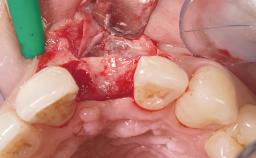

Late Flapless Placement of an Implant in a Maxillary Left Central Incisor Site

A 39-year-old male patient presented with a chief complaint of discomfort and gingival discoloration around his maxillary left central incisor. He was in good general health and was a non-smoker. His past dental history was significant because of the traumatic fracture of tooth 21 in a sporting accident at age 13. Initial dental treatment included endodontic therapy and a full-coverage restoration. The patient became symptomatic 5 years later, when structural failure of the tooth resulted in the dislodgment of the crown. Endodontic retreatment, apical surgery, and post-and-core restoration were performed.

Bone Augmentation Horizontal|Staged

Augmentation Materials Xenogenous|Membrane

Soft Tissue Grafting Simultaneous

Soft Tissue Anatomy Intact Defective

Bone Volume Horizontally and vertically sufficient Horizontally deficient Deficient vertically or deficient vertically AND horizontally